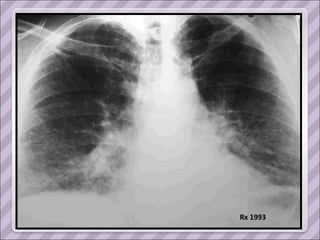

Rx 1993

TAC 1993

APP Sarcoidosis torácica  (1993, dx por biopsia ganglionar del mediastino. Estadio II) Compromiso cutáneo (eritema nodoso recurrente y refractario en MMII), ocular (uveítis) y del SNP ( mononeuropatía múltiple). Tratamiento prolongado con corticoides y azatioprina.  Cushing exógeno Diabetes inducida por esteroides Serología positiva para Hepatitis C en 2006